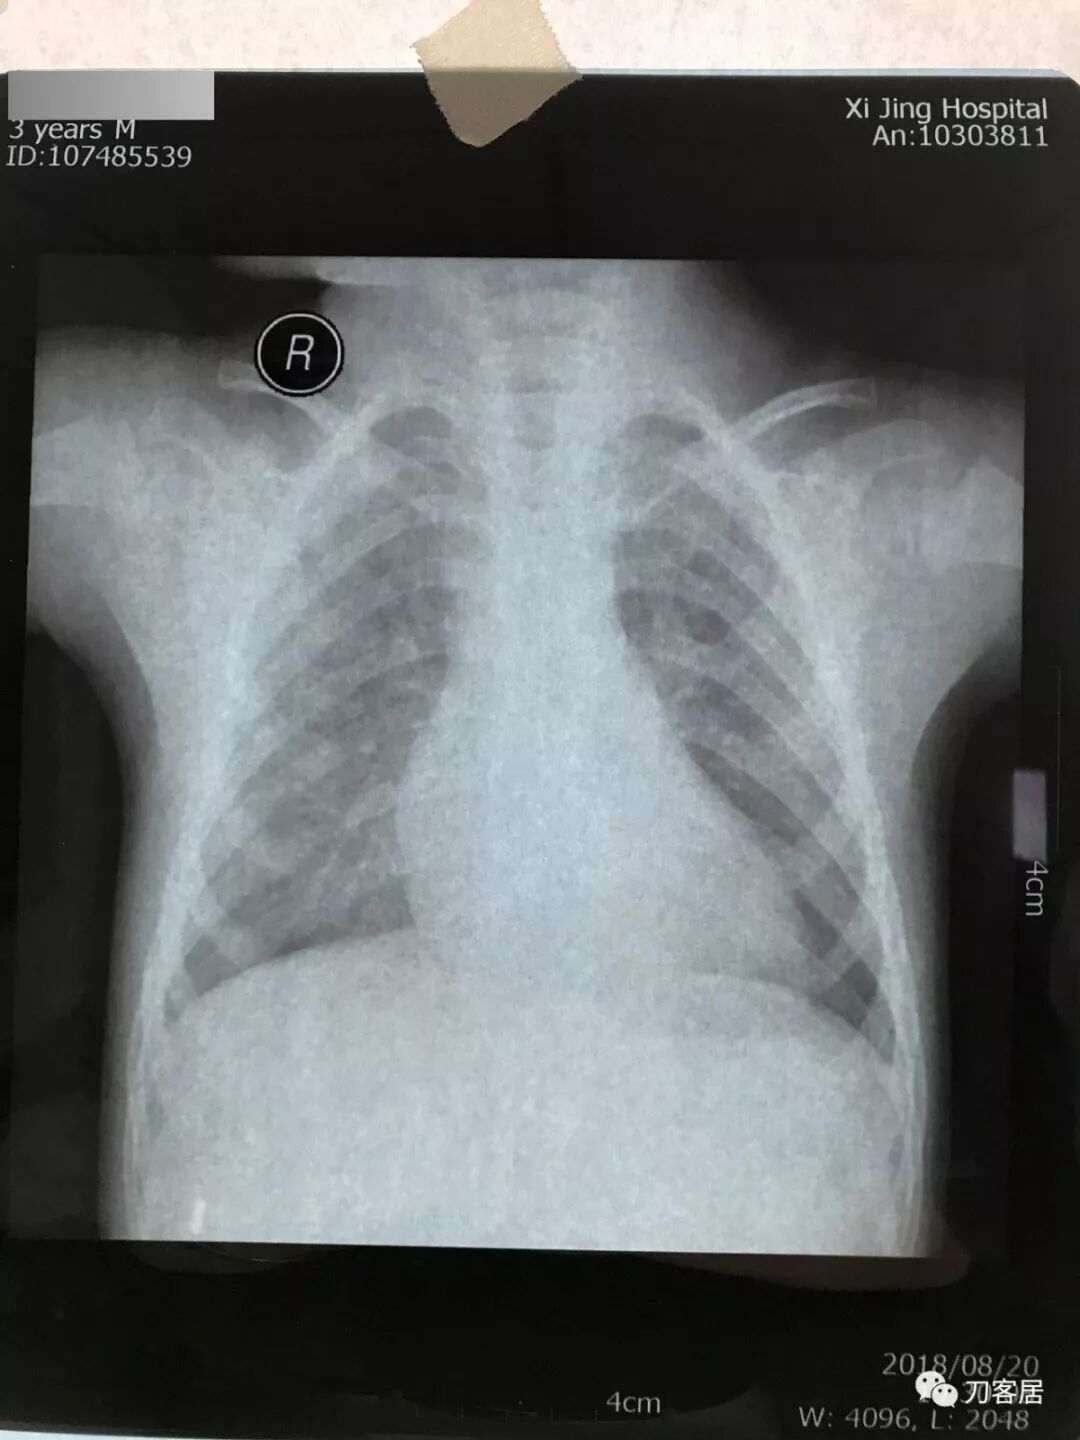

如果用的是电脑显示器翻拍片子,按照第6条将显示屏变白色后,将片子贴于显示器上(图10)进行拍照(图11,图12)。

图10

图11

图12